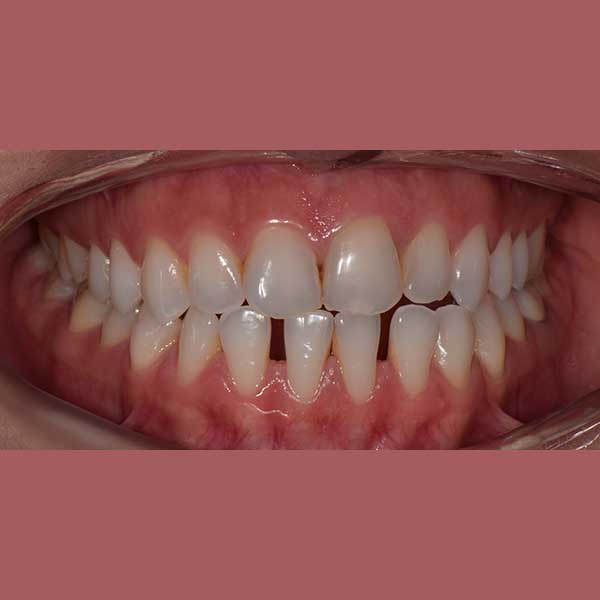

BEFORE

This patient has suffered from spaces between her lower teeth due to an unknown reason, and by examining the teeth, I found that the gums were healthy and fixed braces were installed and the spaces were closed successfully in addition to the paving of the upper teeth successfully as well.